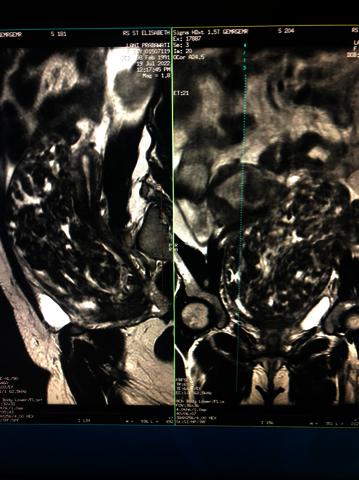

Image

WhatsApp Image 2022-08-18 at 7.06.47 PM.jpeg Download (138kB) | Preview |

The 20-25% incidence of uterine myoma often experienced by women in childbearing age and 2% of these uterine myomas attach and grow in the uterine cervical area. The chief complain of cervical myom are lumps in the lower abdomen that are getting bigger and pressing on the urinary bladder cause difficulty in urinating and are accompanied by bloody urine, although the amount of menstrual blood is still within reasonable limits. Like uterine myomas, cervical myomas are not fused with the myometrial lining but are covered by thin connective tissue on the surface.The procedure of cervical myoma based on ACOG (American College of Obstetrics and Gynecology) is hysterectomy if the patient no longer wants to get pregnant, or myomectomy if the patient still wants to have children. Both of these actions have a very high risk in which vascularization in the pelvic area will be very complex, pressure on cervical myoma will have a high risk of injuring the urinary bladder mucosa and when setting aside the lower segment of the uterus there is a risk of injury. We present a 38-year-old woman with 30x 26 x 22 cm giant cervical myoma and secondary infertility that was treated with challenging laparotomi myomectomy in colaboration with urologist to preserve fertility. There was a tear in the upper part of the urinary bladder which was elongated with irregular edges measuring 12 x 5 cm after enucleation cervical myoma. The tear was repaired immediately and there are no complications in the form of vesico-vaginal fistulas or vesico-cervical postoperatively.